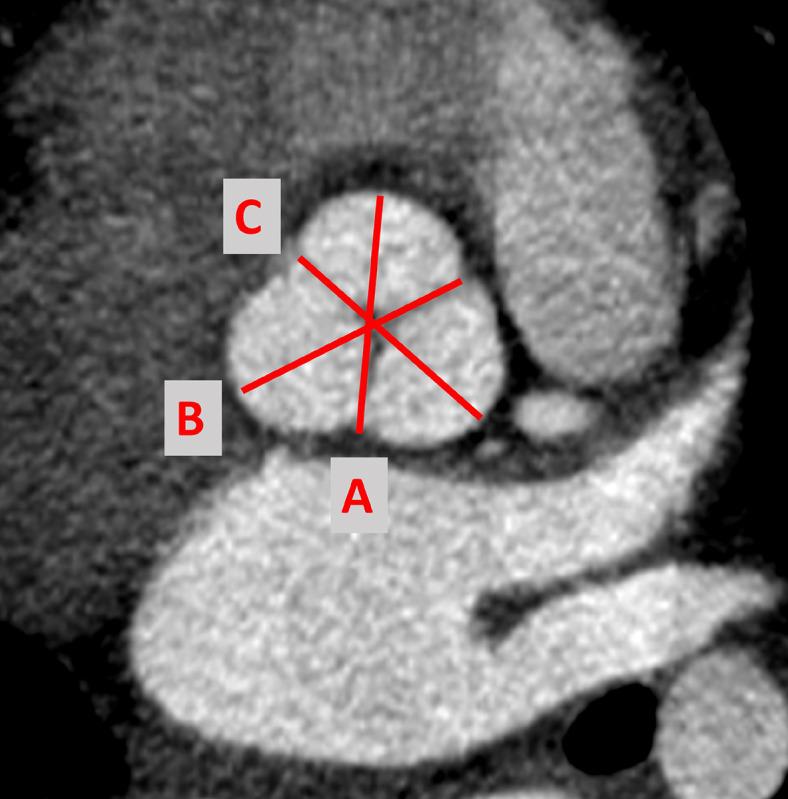

Aortic root, ascending aorta, aortic arch, and descending aorta were measured in systole and diastole in 100 subjects who had ECG-gated CTA at our center between January 2015 through December 2020 and met our inclusion criteria. The allometric exponent (AE) for each parameter was derived, and the parameter/body surface area (BSA) was established using the previously described methods. Using this data, normalized mean, cross-sectional area, and standard deviation were calculated. Z-score curves were plotted in relation to the BSA for all measurements.

对2015年1月至2020年12月期间在我们中心接受心电图门控CTA且符合纳入标准的100名受试者,在收缩期和舒张期测量主动脉根部、升主动脉、主动脉弓及降主动脉。得出每个参数的异速生长指数(AE),并使用先前描述的方法确定参数/体表面积(BSA)。利用这些数据,计算标准化均值、横截面积及标准差。针对所有测量结果,绘制相对于BSA的Z评分曲线。